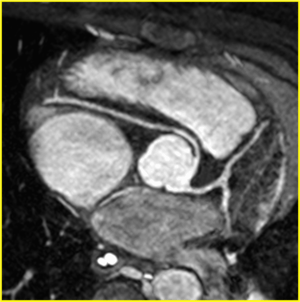

| Anomalous origin of the right coronary artery from the left coronary sinus by CMR with an inter-arterial, potentially dangerous course | |